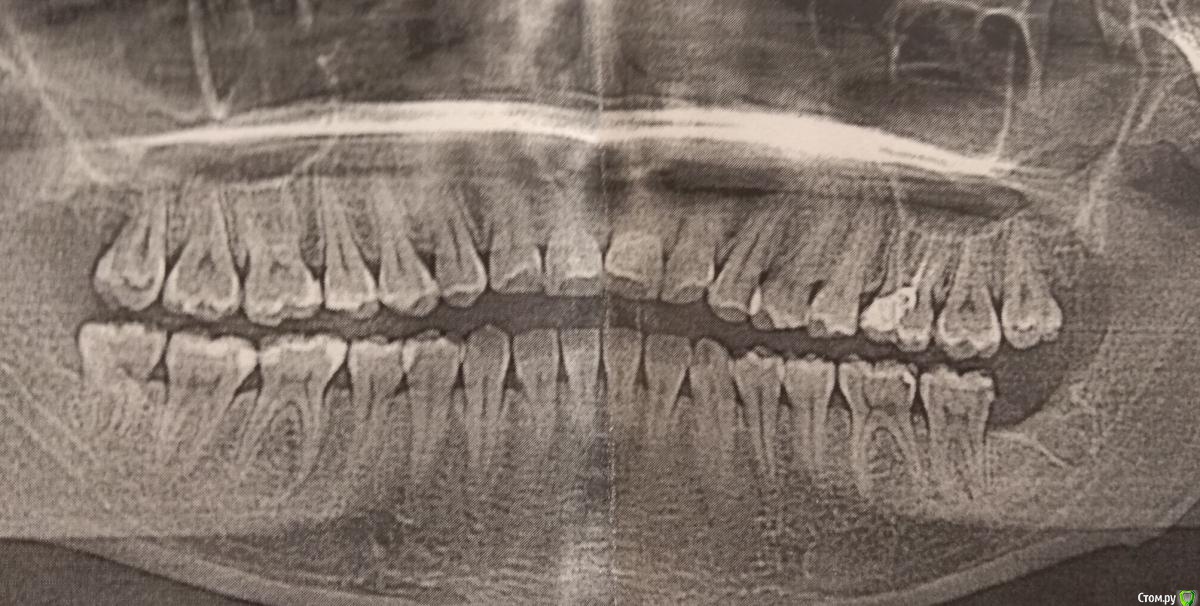

Zlata-doctor Опубликовано 12 апреля, 2020 Поделиться Опубликовано 12 апреля, 2020 что делали с 7 зубом? Есть актуальный снимок? Ссылка на комментарий

IAmValeria Опубликовано 12 апреля, 2020 Автор Поделиться Опубликовано 12 апреля, 2020 что делали с 7 зубом? Есть актуальный снимок?Вот снимок, буквально пару дней назад сделан. В семёрке лечили кариес. Ссылка на комментарий

Zlata-doctor Опубликовано 13 апреля, 2020 Поделиться Опубликовано 13 апреля, 2020 Валерия, добрый день! Я очень Вам сочувствую.Я думаю,что у вас скоро все должно пойти на улучшение.Я считаю, что причина болей не в конкретном зубе. Во-первых, слишком долго все это продолжается. Обычно осложненный кариес с интенсивными болями довольно быстро ( за несколько дней) куда-то разрешается: или проходит боль, то есть переходит в хроническую фазу, или обостряется с отеком и даже гноем итд. У вас более месяца ничего этого нет. Поэтому можно думать о причине непосредственно в области удаленного зуба. Тем более, что был удален зуб мудрости, который чаще всего и дает такие осложнения. Поэтому я бы очень осторожно предпринимала попытки лечить другие зубы в этой области!!! Это необоснованно!!Честно говоря, ваш снимок не показывает ничего подозрительного. Я думаю, что у вас имеется неврологическое поражение. К сожалению, такое состояние не проходит быстро и очень мучительно. Также нет достоверных данных, что витаминные препараты типа Мильгаммы или какие-то БАДы ускоряют процесс восстановления. Поэтому в такой ситуации остается ждать и обезболиваться. Препарат выбора здесь Габапентин , Лирика-неврологические препараты, которые должен назначить только невролог. Обратитесь к грамотному неврологу и выздоравливайте, пожалуйста. 1 Ссылка на комментарий